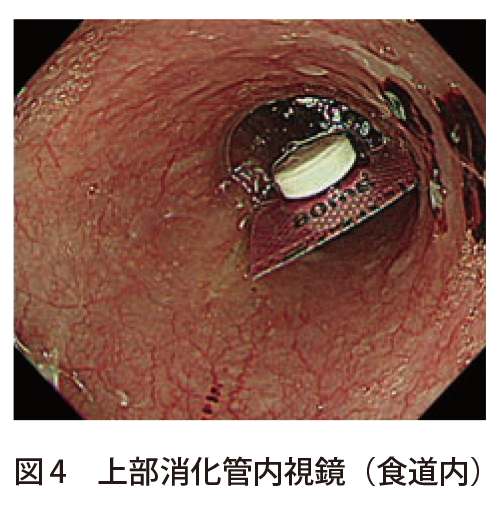

I M A Radiographer Radiotechnologist 私は放射線技師 ブログ

食道にptpシート 内視鏡で除去も 医療機能評価機構 誤飲報告相次ぎ

Http Www Jshp Or Jp Cont 10 0922 5 Pdf

Https Www Kuhp Kyoto U Ac Jp Wwwrisk News Jyohou107 Pdf

Http Www Yamaguchi Med Or Jp Wp Content Uploads 2019 10 2019houan 97 Pdf

犬の誤飲によるptpシートを内視鏡で摘出除去 石川台どうぶつ病院